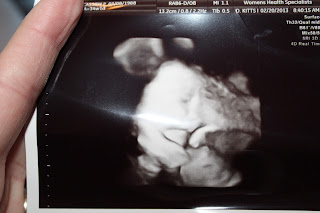

I didn't change the picture just because it verifies preggo brain...

This is Week #: 34 Weeks